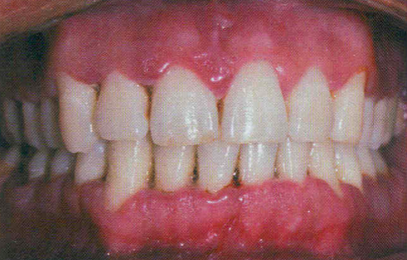

Necrotizing Ulcerative Gingivitis (NUG)

Associated with specific bacteria: Fusobacterium nucleatum, Prevotella intermedia, Porphyromonas gingivalis, Treponema spp., and Selenomonas spp.

Frequently occurs in the presence of psychological stress

WWI; “trench mouth”

Immune suppression (AIDS, infectious mononucleosis)

Foul odor

Blunted papillae,“punched out”

Gray pseudomembrane